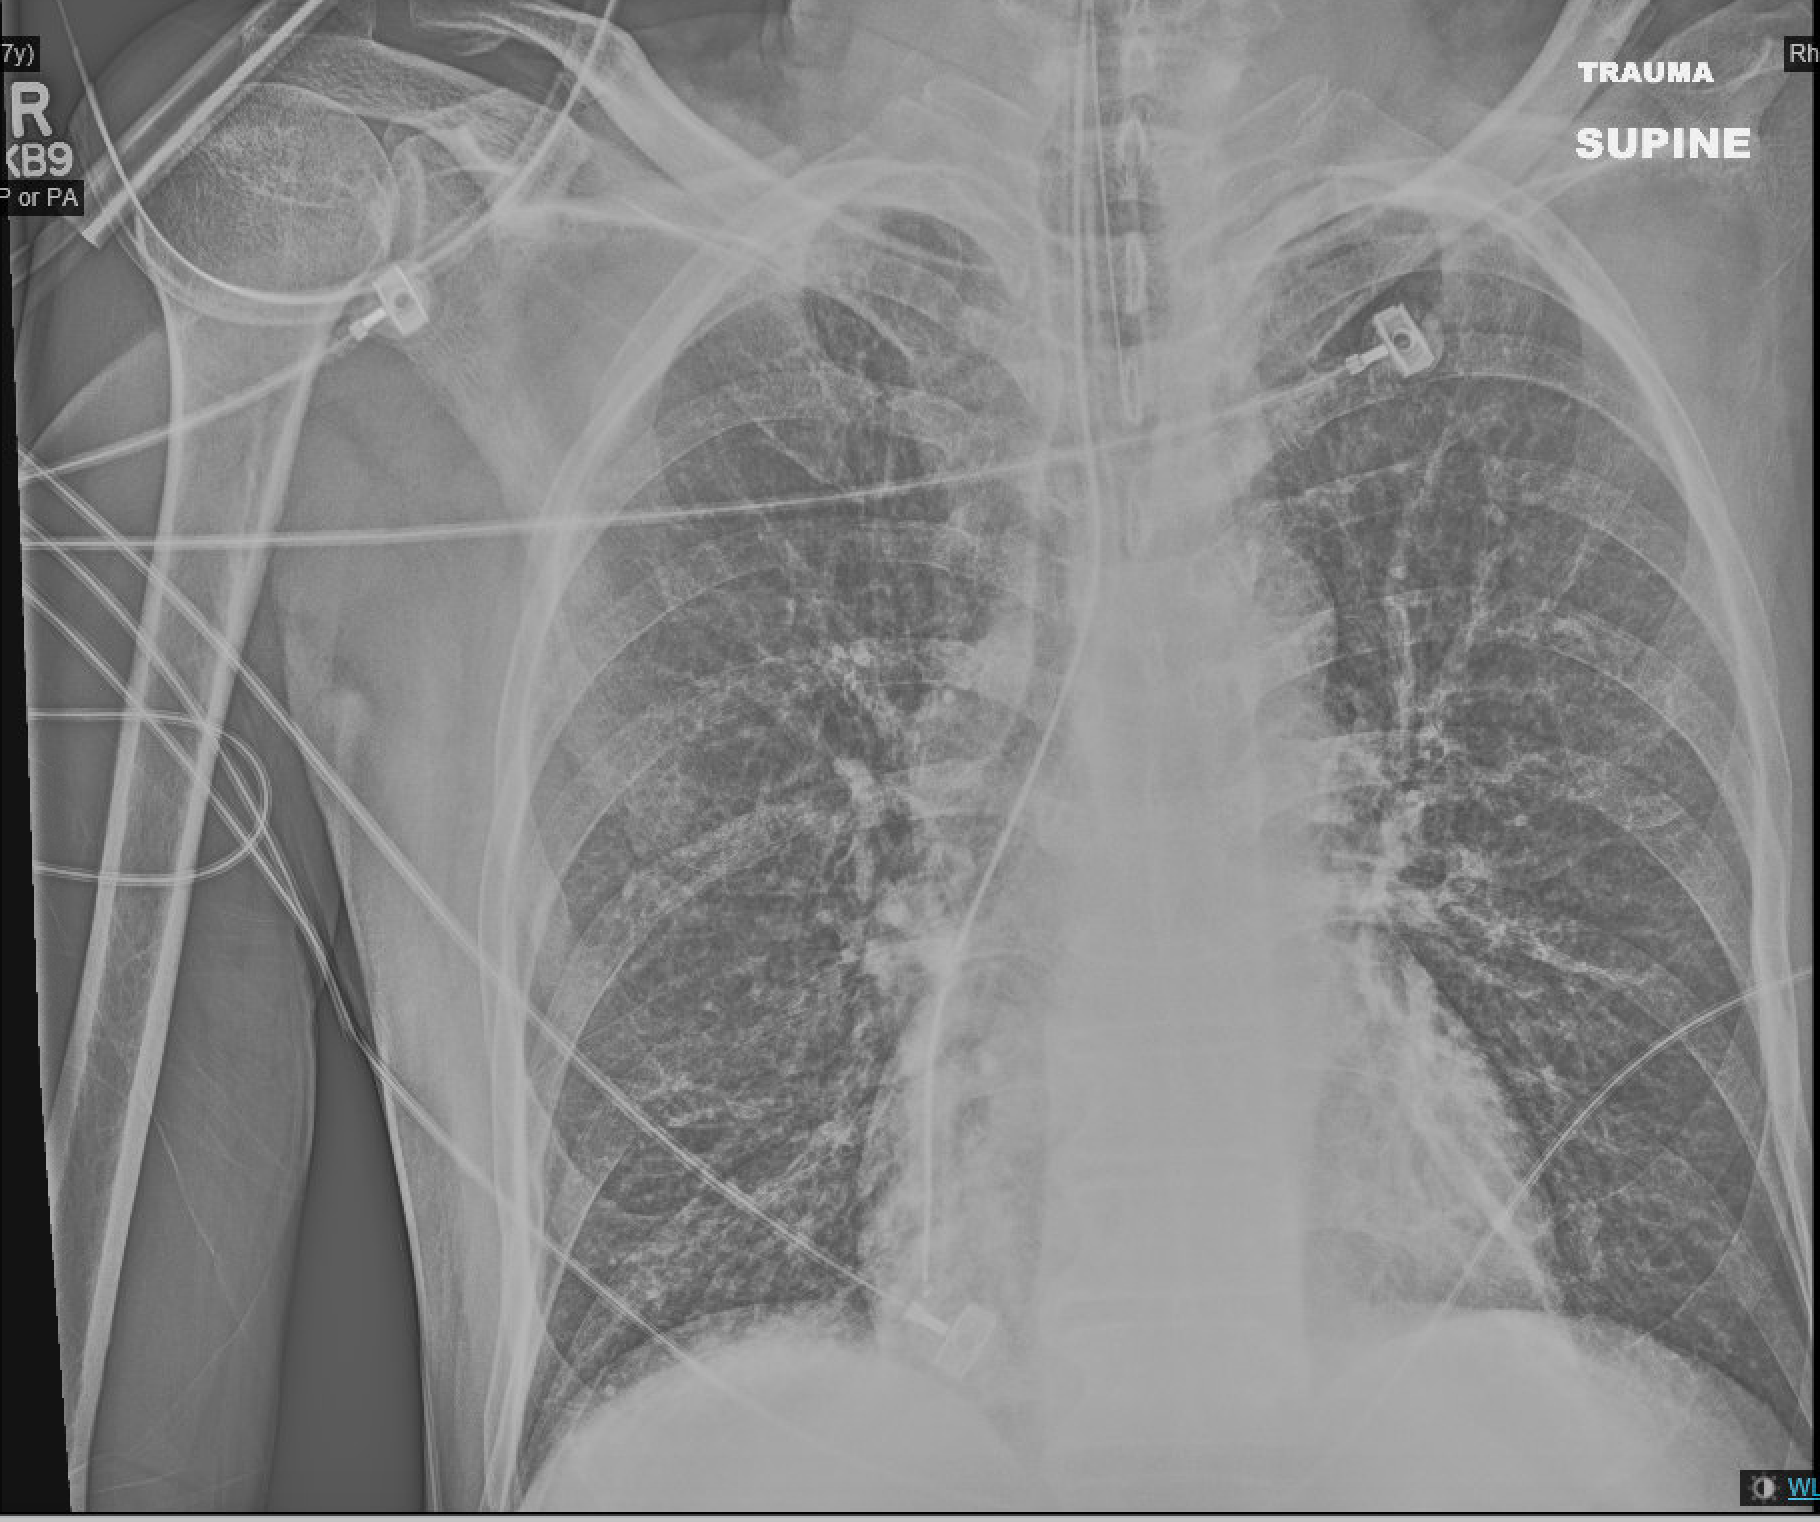

Case 8: Find the abnormality.

Case 8 answer: This patient has a left pneumothorax. This patient is supine at the time of this image (like many of our back-boarded and collared trauma patients). Notice the abnormally deep costophrenic angle on the left. This is known as the deep sulcus sign and is present because air collects in the non-dependent potions of the pleural space (anteriorly and basally when the patient is supine, apex when the patient is upright).